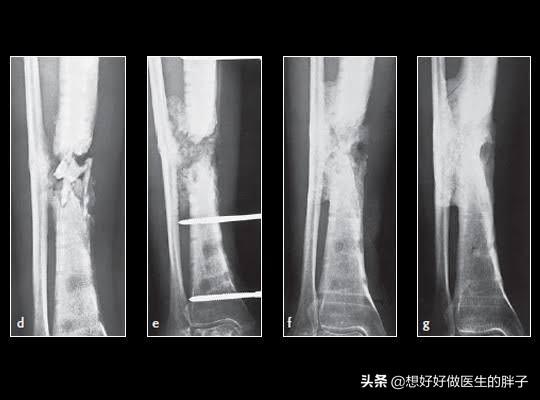

第一,一定要去复查骨折x线的情况,是否有明显的骨不连,也就是骨折没有愈合,骨折之间还存在着明显的松动,这样在活动的时候就会刺激骨折周边软组织等结构,导致肿胀不消退。另外七个月的时间,如果是手术治疗,是否存在折端的感染,在x线上也会有体现,长期的慢性感染也会导致肢体的肿胀,而且患者不一定会有明显发热等症状。

●如果存在骨不连的情况,7个月的时间对于胫腓骨粉碎骨折来说还不能说没有愈合的希望,因为这个位置由于其特有的血供特点,一旦骨折愈合就会比较慢,可以尝试去当地医院进行冲击波治疗,尤其是聚焦式冲击波治疗,对于骨不连有比较好的治疗效果,不需要2次开刀就有促进骨折愈合的疗效。目前有研究数据显示冲击波治疗骨不连有70%左右的愈合几率,所以建议还是先进行保守治疗三个月无效再考虑开刀手术治疗骨不连。而骨头愈合了,下肢稳定了,肿胀也就慢慢消退了!

胫腓骨这个位置一旦发生骨折,愈合也比较慢,肿胀消退比较慢,因为这个位置血运相对来讲不是特别的好,即使是体重比较大的人在小腿这个部位也是比较细的,尤其是在胫骨前方这个部位,一般都是皮包着骨头,一旦发生骨折恢复起来比较慢,也是可以理解的!但是7个月的时间如果仍然明显肿胀的话,一定要进行x线的检查以及下肢血管彩超的检查,明确是否有骨不连、骨折的感染或者是下肢血运的问问题。如果检查没有太大的问题,建议要科学的康复锻炼,同时平时注意减少下垂下肢的时间,可以口服一些促进肿胀消退的药物。